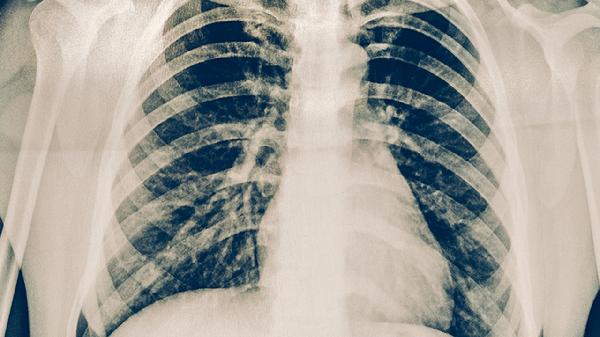

做肺部活檢通常意味著需要通過組織檢查明確肺部病變的性質(zhì)?;顧z有助于診斷肺部腫瘤、感染、炎癥或其他疾病,并確定治療方案。主要方法包括經(jīng)皮穿刺活檢、支氣管鏡活檢和手術(shù)活檢。

1、經(jīng)皮穿刺活檢:這是一種微創(chuàng)檢查,醫(yī)生通過CT或超聲引導(dǎo)將穿刺針插入肺部獲取組織樣本。適用于靠近胸壁的病變,創(chuàng)傷小,但可能引起氣胸或出血。術(shù)后需觀察呼吸情況,避免劇烈活動(dòng)。

2、支氣管鏡活檢:通過鼻腔或口腔插入支氣管鏡,直接觀察氣道并取樣。適用于靠近氣道的病變,患者需局部麻醉。檢查后可能出現(xiàn)喉嚨不適或輕微出血,通常無(wú)需特殊處理。

3、手術(shù)活檢:在無(wú)法通過微創(chuàng)手段獲取組織時(shí),醫(yī)生可能選擇開胸或胸腔鏡手術(shù)。手術(shù)活檢可獲取更大樣本,但創(chuàng)傷較大,需住院觀察。術(shù)后需注意傷口護(hù)理,避免感染。

肺部活檢的風(fēng)險(xiǎn)包括出血、感染和氣胸。術(shù)前需進(jìn)行全面評(píng)估,包括血液檢查、影像學(xué)檢查和肺功能測(cè)試。術(shù)后應(yīng)遵醫(yī)囑休息,避免用力咳嗽,觀察有無(wú)呼吸困難或胸痛等癥狀。